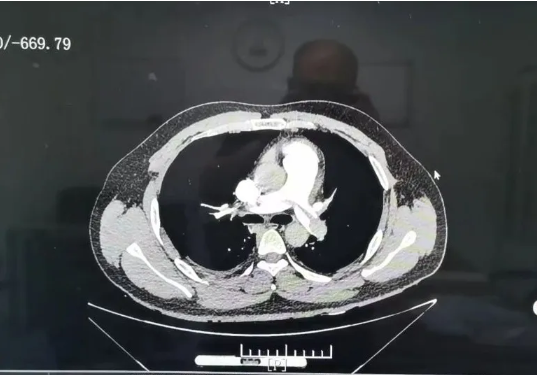

呼吸内科赵丽梅主任凭借丰富经验,立刻想到了“肺栓塞”——这个被称为“沉默杀手”的凶险疾病。结合患者长期久坐的高危病史,医院迅速安排肺动脉CTA检查,半小时内就出了结果:双侧肺动脉主干及分支被血栓广泛堵塞,属于死亡率极高的“高危急性肺栓塞”。